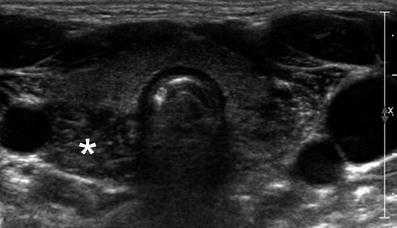

| Фото. А — Поперечный срез тимуса у новорожденного. Б — У детей раннего возраста, особенно при крике, верхняя часть тимуса может подниматься на шею через яремную вырезку, тогда он определяется позади щитовидной железы (звездочка). В — На саггитальном срезе хорошо видно, что тимус (эктопическая долька на шее) гипоэхогенный по сравнению с щитовидной железой. | ||